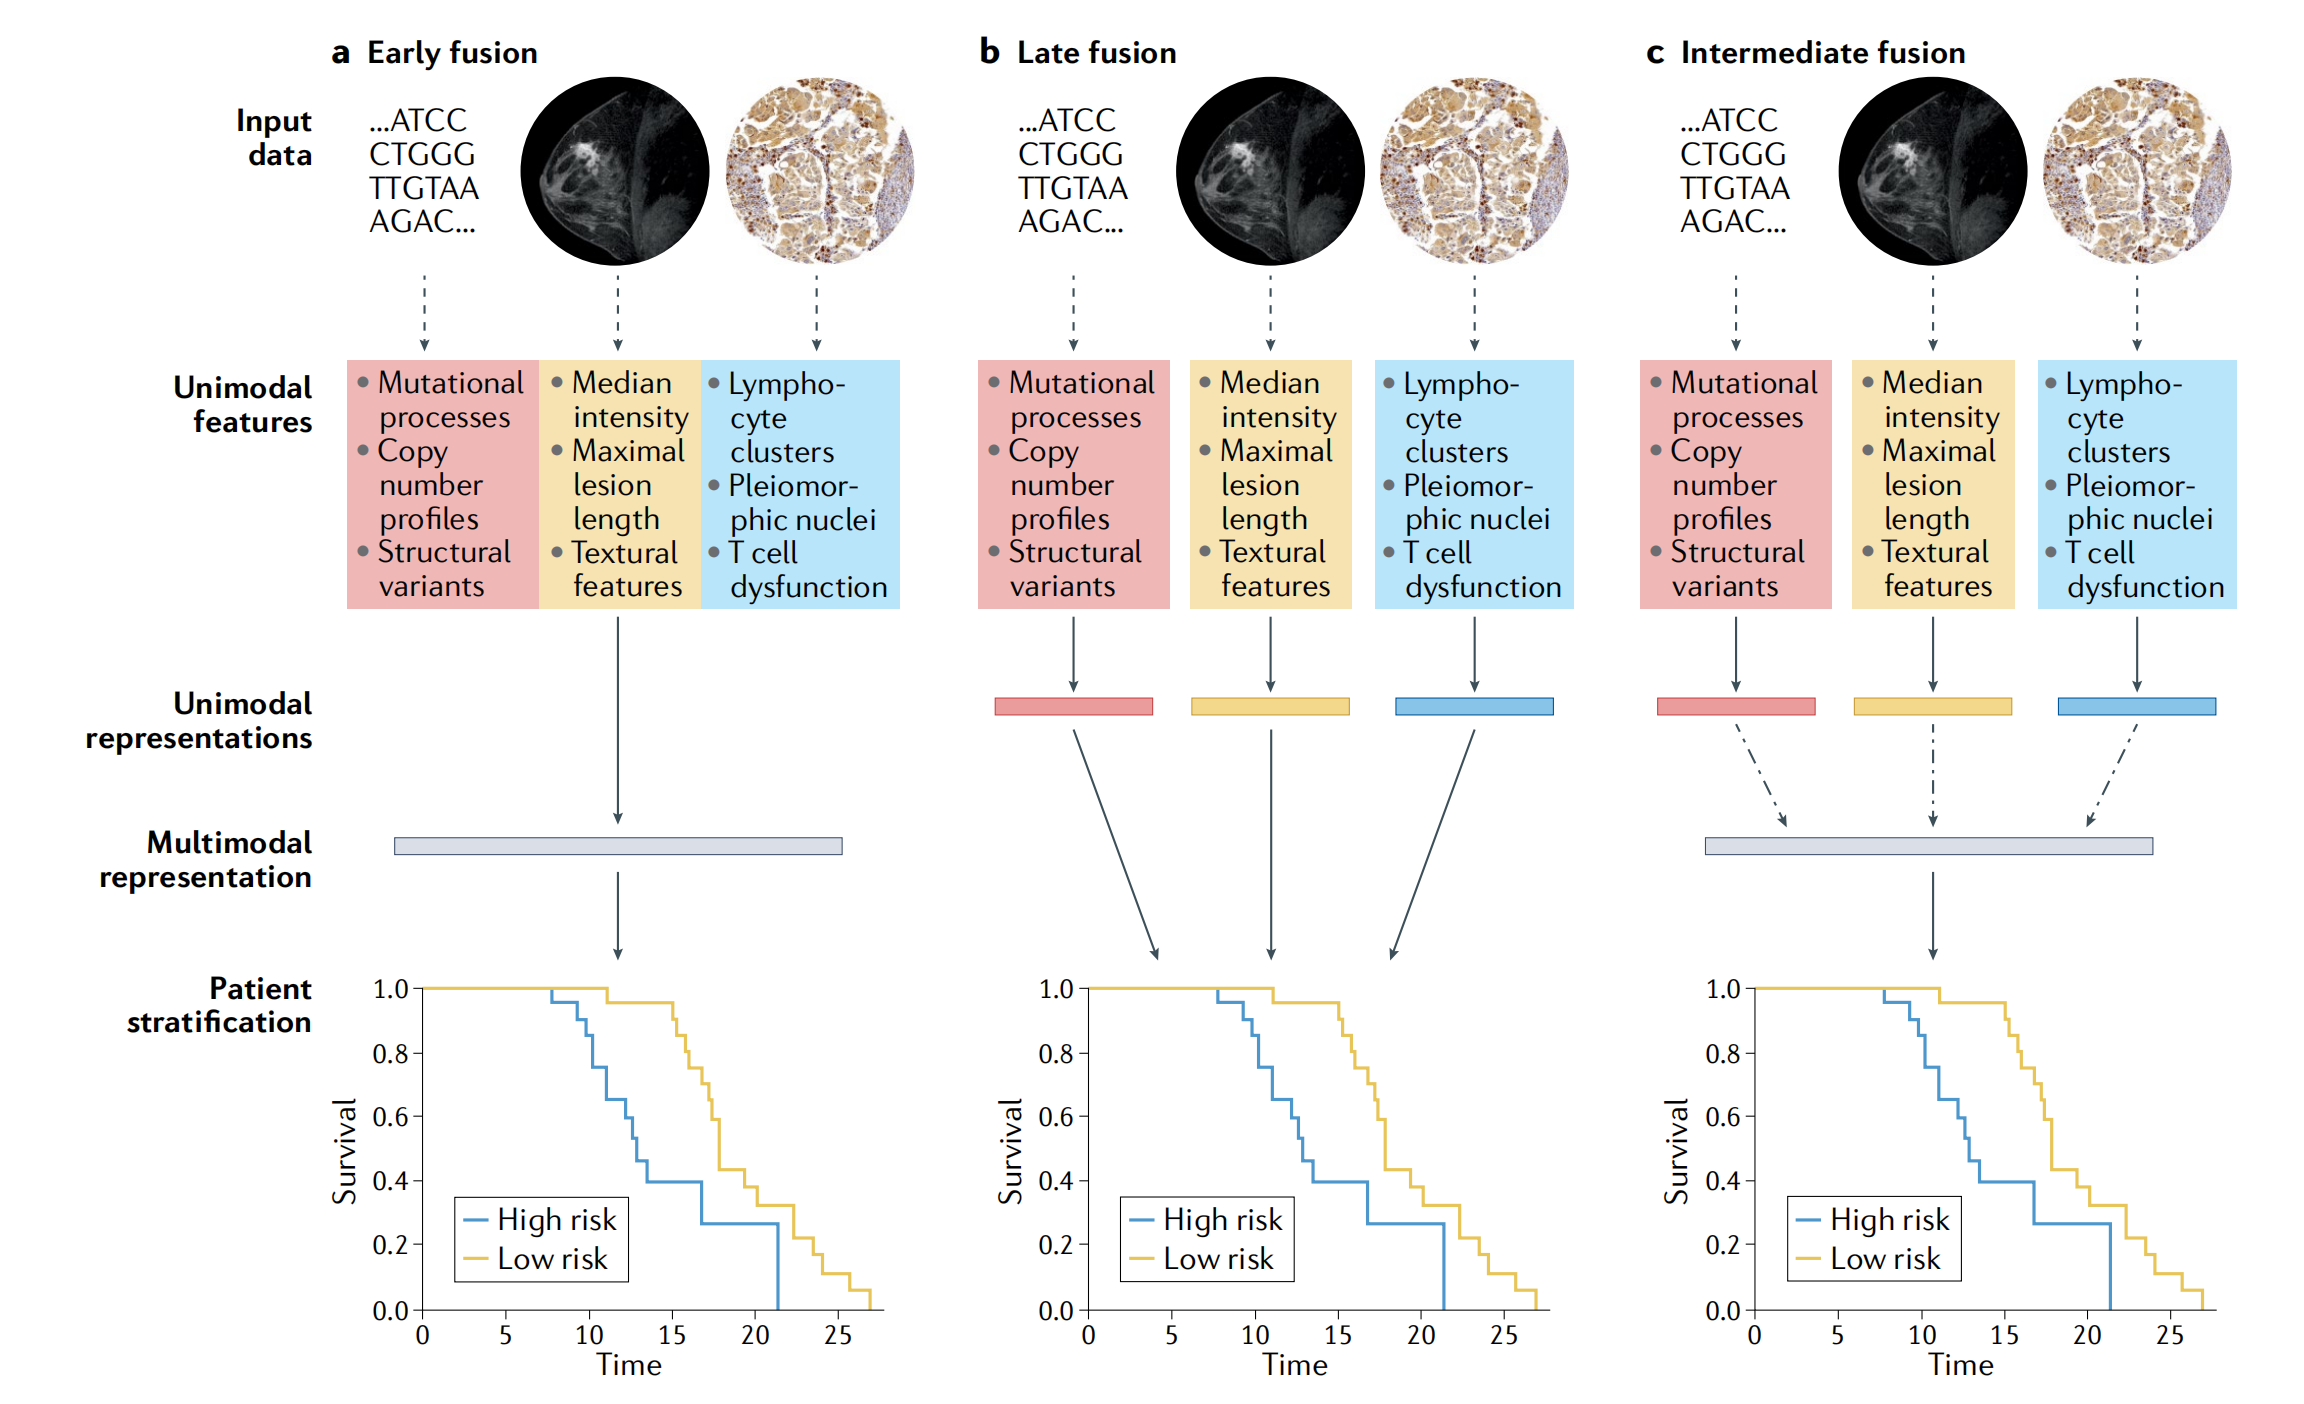

多模态方法的一个主要设计选择是每个数据输入在联合表示被编码之前应该被建模到何种程度(图3)。

- 在早期融合架构中,特征在开始时简单地串联起来,并用于训练单个模型(图3a)。

- 在另一极端,晚期融合架构完全单独建模单模态数据,然后聚合学习的参数或导出的分数(图3b)。

- 中间融合架构开发每个模态的表示,然后建模跨模态交互,再进行联合建模(图3c)。

大多数多模态架构的参数数量多于其单模态对应物,这使得它们容易过拟合(学习表示训练数据过于精确,导致不可泛化的模型),这在监督学习环境中可能反而导致性能更差【62】。解决这个问题的一个机制是将估计的泛化误差纳入训练目标,使用技术如梯度混合,这是一种根据估计的泛化误差对每个单模态贡献到整体损失进行加权的技术【62】。

图 3 展示了在设计包含基因组学、放射学和组织病理学数据的多模态模型时所面临的几种关键决策。这些决策涉及到如何在模型中整合来自不同数据源的信息。

图中描述了三种不同的融合(fusion)架构:

-

早期融合(Early fusion):

- 在早期融合中,不同模态的特征在模型训练的最初阶段就被简单地拼接(concatenated)在一起。

- 这些组合特征随后被用来训练一个单一的模型来进行预测或分类。

- 早期融合的模型需要较少的参数,因为它直接在所有可用数据上训练,但可能难以捕捉不同模态间的复杂交互。

-

晚期融合(Late fusion):

- 在晚期融合架构中,每种单模态数据首先被单独且完整地处理。

- 每个模态的模型独立地学习并产生一个单模态分数(score),然后这些分数被聚合(aggregated)或通过简单的算术操作结合起来。

- 晚期融合允许每个模态独立贡献信息,但可能不如早期融合那样能够充分利用模态间的互补信息。

-

中间融合(Intermediate fusion):

- 中间融合是两种极端方法的折衷,它首先独立处理每种单模态特征,然后开发每种模态的表示(representation),接着在联合建模之前对模态间的交互进行建模。

- 这种架构可能包含可学习的参数,允许模型学习如何在不同模态之间传递和整合信息。

图 3 还指出,多模态模型通常比单模态模型有更多的参数需要拟合,这使得它们更容易过拟合(即在学习训练数据时过于精确,导致模型泛化能力下降)。为了解决这个问题,可以采用一些技术,比如梯度混合(gradient blending),这是一种根据每种单模态贡献的估计泛化误差来加权整体损失的技术。

此外,图中还提到了深度学习(DL)架构,包括卷积神经网络(CNNs)和循环神经网络(RNNs),以及它们在不同数据类型上的应用。例如,CNNs 用于从图像中学习纹理模式,而 RNNs 用于处理时间序列数据,如实验室值的时间序列。